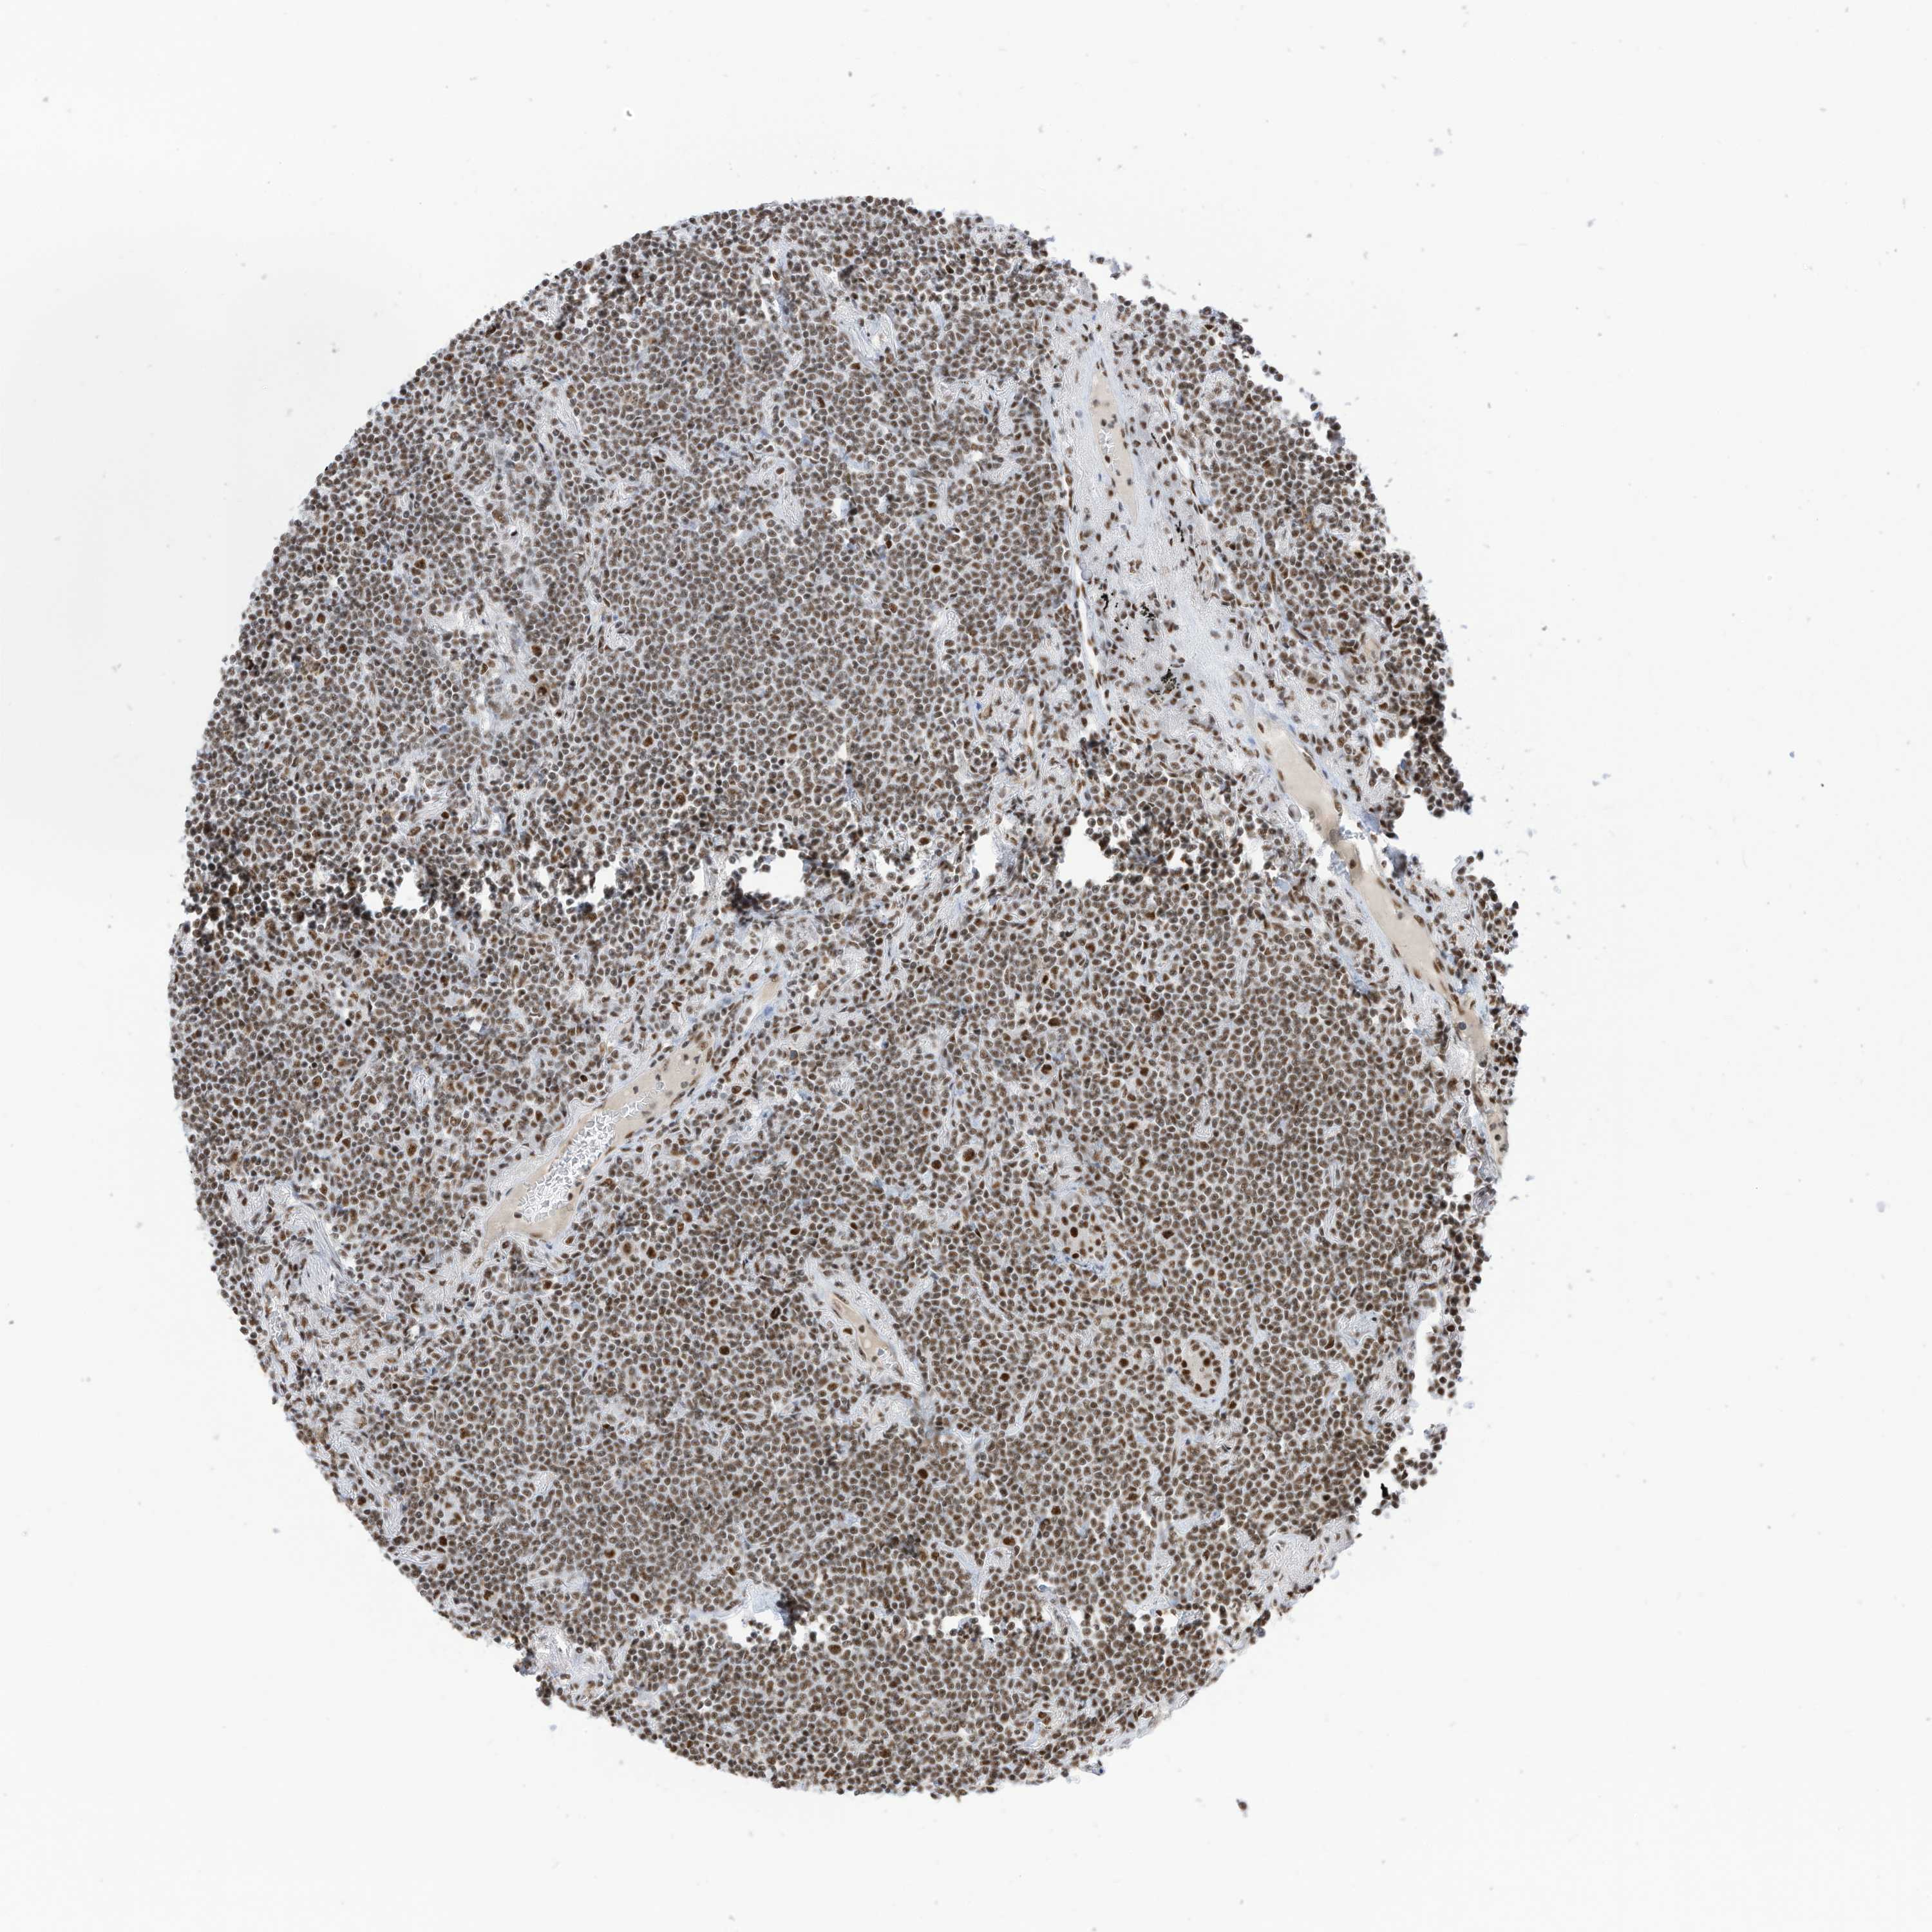

LYMPHOMA - Protein expressioni

A mouse-over function shows sample information and annotation data. Click on an image to view it in a full screen mode. Samples can be filtered based on level of antibody staining by selecting one or several of the following categories: high, medium, low and not detected. The assay and annotation is described here.

Antibody stainingi

Antibody staining in the annotated cell types in the current human tissue is reported as not detected, low, medium, or high, based on conventional immunohistochemistry profiling in selected tissues. This score is based on the combination of the staining intensity and fraction of stained cells.

Each image is clickable and will lead to virtual microscopy that enables deeper exploration of all samples and also displays staining intensity scores, fraction scores and subcellular localization as well as patient and tissue information for each sample.

Antibody HPA032054

Staining

High

Intensity

Strong

Quantity

>75%

Location

Nuclear

Hodgkin's disease, NOS

Malignant lymphoma, non-Hodgkin's type, High grade

Malignant lymphoma, non-Hodgkin's type, Low grade